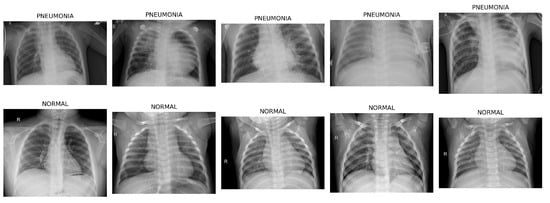

2. Pneumonia Chest X-ray Dataset: Sourced from pediatric patients aged 1 to 5 years at Guangzhou Women and Children’s Medical Center, this dataset, Figure 7, comprises 5863 anterior/posterior chest X-ray images labeled as pneumonia and normal [50].

Figure 7. Sample images of Pneumonia Chest X-ray Dataset.